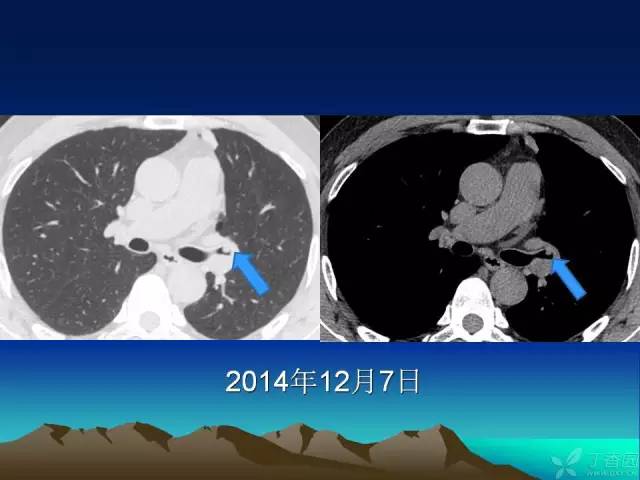

【PPT】早期肺癌易漏诊征象分析